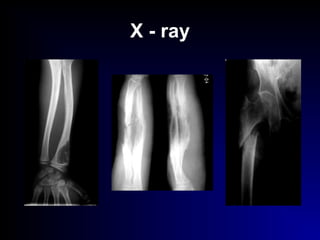

X - ray

 Special investigations :

- X- ray

- C.T.

- M.R.I.